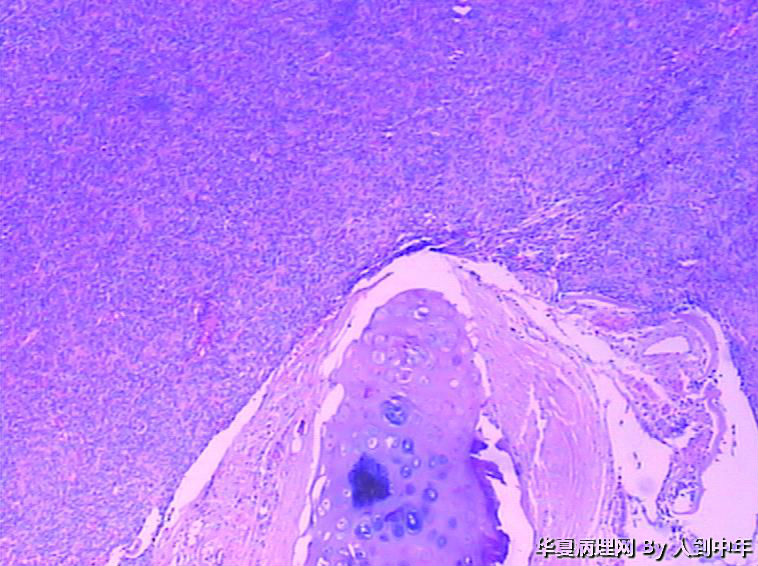

肺部肿瘤--类癌?求助大家

患者,男性,72岁,右肺中叶占位,肺门部肿物,散在多结节状,直径0.2-2.2cm。

• 肺部肿瘤--类癌?求助大家图3

图3

NT。需计数分裂像分级。

低分化癌,看到有腺样结构,肿瘤多结节,也要排除转移。

低分化癌,可能伴神经内分泌分化。不能标记也要建议会诊,去不去是他们的事

癌,微囊、细胞梭形或立方、癌巢周边细胞见栅栏状,不能排除基底细胞样癌。多结节,也要排除转移性涎腺型恶性肿瘤,腺样囊腺癌等。